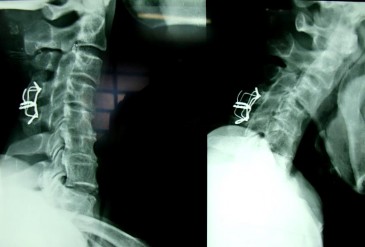

SAU MỔ 3 THÁNG: 29 - 8 – 2008

(Không di lệch thứ phát, chỉ thép tốt) THẲNG NGHIÊNG

SAU MỔ 3 NĂM: 5 - 3 – 2012

(Liền xương độ I. Tình trạng chỉ KHX tốt) THẲNG NGANG

(Gù tròn, cứng C3-C7 do thoái hóa)

(Vận động CSC bị hạn chế)